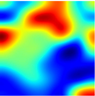

4.5. Explaining COVID-19

| X-ray | VGG16 | ResNet50 | Inception | Ensembled (Ours) | Uncertain-CAM (Ours) | Ground Truth |

![]() | ![]() | ![]() | ![]() | ![]() | ![]() | ![]() |